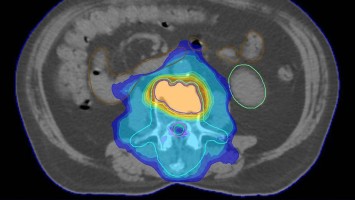

Neues in der Radiochemotherapie von Kopf-Hals-Tumoren

Erste Studien deuten darauf hin, dass eine Deeskalation der Radiochemotherapie bei nichtmetastasierten Kopf-Hals-Tumoren möglich ist – insbesondere bei HPV-positiven Karzinomen. Hypoxiesensitive Bildgebung könnte die Patientenselektion unterstützen. Gleichzeitig zeichnet sich die perioperative Checkpointinhibition als potenzieller neuer Standard bei resektablen HNSCC ab.

Kutane Arzneimittelreaktion/© Hötzenecker, W., Heimlich-Manöver/© Widmer, N; Heimes, D / all rights reserved Springer Medizin Verlag GmbH, Aufbau bei einer endoskopische Mittelohrchirurgie/© Mir-Salim P., Berlin, Wespen auf Stein/© merlion / Getty Images / iStock (Symbolbild), Schilddrüse einer Patientin wird untersucht/© Werner / stock.adobe.com (Symbolbild mit Fotmodellen), Volumetrie des Bulbus olfactorius/© Keweloh S.. et al. doi.org/10.1007/s00106-025-01650-z unter CC-BY 4.0, Augen und Nase einer Frau/© AlexanderFord / Getty Images / iStock (Symbolbild mit Fotomodell), Eine ältere Frau schaut in die Ferne/© RgStudio / Getty Images / iStock (Symbolbild mit Fotomodell), Transnasales Ösophagoskop/© F. Michel, Seeheim-Jugenheim, Ex vivo konfokales Laserscanmikroskopiebild eines Morbus Bowen/© Grunewald S et al. / all rights reserved Springer Medizin Verlag GmbH, Einweckglas mit Hering/© FoodieMedia / Getty Images / iStock (Symbolbild), Zwei Injektionspens mit Semaglutid/© Kassandra / Stock.adobe.com, Gewitter mit Blitzschlag/© solarseven / Getty images / iStock, Ulzerative Form des oralen Lichen planus/© Abdusalamov K. et al. doi.org/10.1007/s00105-025-05540-x unter CC-BY 4.0, Otitis externa/© Dr. P. Marazzi / Science Photo Library (Symbolbild), VMAT-Bestrahlungsplan einer definitiven Radiochemotherapie eines linksseitigen, lokal fortgeschrittenen Tonsillenkarzinoms/© Schnellhardt, S et al. / all rights reserved Springer Medizin Verlag GmbH, Frau hustet/© Suzi Media Production / Getty Images / iStock (Symbolbild mit Fotomodell), Tympanometrie bei einer Frau/© Viacheslav Yakobchuk (Symbolbild mit Fotomodell), Stimmlippeninjektion in der HNO-Praxis/© Markus Hess, Mann erhält eine Spritze im Gesicht/© Alvaro / Stock.adobe.com (Symbolbild mit Fotomodell), Ein Arzt sprüht ein antimikrobielles und entzündungshemmendes Spray in den entzündeten Hals eines Mädchens./© HENADZY / Stock.adobe.com (Symbolbild mit Fotomodell), Junger Mensch bekommt Spritze verabreicht/© mapo / Getty Images / iStock (Symbolbild mit Fotomodellen), Bestrahlungsplans einer Wirbelsäulenmetastase eines oligometastasierten Prostatakarzinoms/© Springer Medizin Verlag GmbH, Cholesterolgranulom im MRT/© Frederik F/ all rights reserved Springer Medizin Verlag GmbH, Schimmelbefall an der Wand/© Bigy / Stock.adobe.com (Symbolbild), Rasterelektronenmikroskopische Aufnahme von Nanopartikeln/© Hansen S. et al. doi.org/10.1007/s00106-025-01633-0 unter CC-BY 4.0, Medulläres Schilddrüsenkarzinom linker Schilddrüsenlappen in der Sonographie/© Lorenz K et al. / all rights reserved Springer Medizin Verlag GmbH, Sonnenhüte (Echinacea)/© Wieland Teixeira / Getty Images / iStock (Symbolbild mit Fotomodell), Körperstereotaxie einer Lebermetastase im Segment VIII am MR-LINAC/© Ehret, F. et al. / all rights reserved Springer Medizin Verlag GmbH, Eine ältere Frau riecht an einem Basilikumblatt/© Halfpoint / Stock.adobe.com (Symbolbild mit Fotomodell), Mann hustet/© kostyha / stock.adobe.com (Symbolbild mit Fotomodell), Titel/© J. Hornung, Erlangen, Senior hält sich vor Schmerzen an den Hals/© brizmaker / Getty Images / iStock (Symbolbild mit Fotomodell), Chor von älteren Menschen/© Highwaystarz-Photography / Getty (Symbolbild mit Fotomodellen), Eine junge Frau spült sich mir einer Nasenspülung die Nase/© puhhha / Getty Images / iStock (Symbolbild mit Fotomodell), Kleiner Junge mit Pille auf der Zunge/© redpepper82 / stock.adobe.com (Symbolbild mit Fotomodell), Frau mit Kopfschmerzen/© MaximFesenko / Getty Images / iStock (Symbolbild mit Fotomodell), Normaler Verlauf nach Hirntumor?/© Wolfgang Freund, Szintigraphie der Schilddrüse mit zwei Knoten/© AniphaeS / Getty Images / iStock, Patient mit Bauchschmerzen beim Arzt/© anon / Stock.adobe.com (Ausschnitt; Symbolbild mit Fotomodellen), Mann erleidet Schwindel/© Tunatura / Getty Images / iStock (Symbolbild mit Fotomodell), Ärztin untersucht ältere Frau/© peopleimages.com / stock.adobe.com (Symbolbild mit Fotomodellen), Infusion/© georgeoprea9 / Getty Images / iStock, Frau wird Blut abgenommen/© andresr / Getty Images / iStock (Symbolbild mit Fotomodellen), Junge Ärztin vor einem Triage-Zelt/© Milos / Stock.adobe.com (Symbolbild mit Fotomodell)